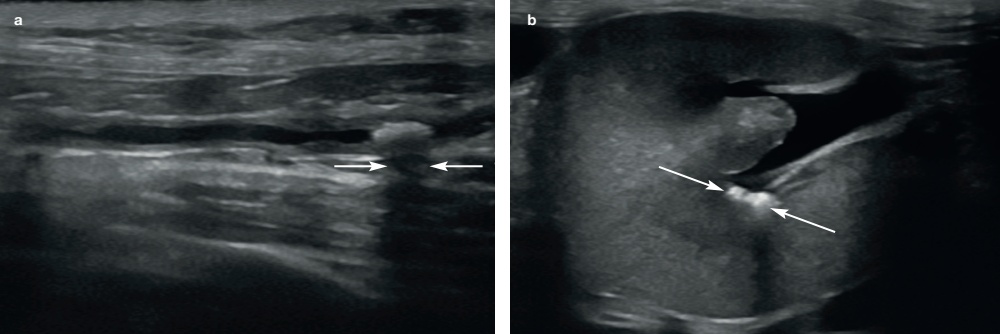

요관 확장의 원인은 이소성 요관(ectopic ureter; 고양이는 드물게 발생), 신우신염(pyelonephritis), 상행성 감염(ascending infection), 폐색(obstruction) 등입니다. 가장 흔한 요관 폐색의 원인은 요관결석입니다. 대부분의 고양이에서 요관결석은 수산칼슘(calcium oxalate) 성분이며, 요관 내 강한 고에코성을 나타나고 후방에 음향그림자를 형성합니다(그림 5).